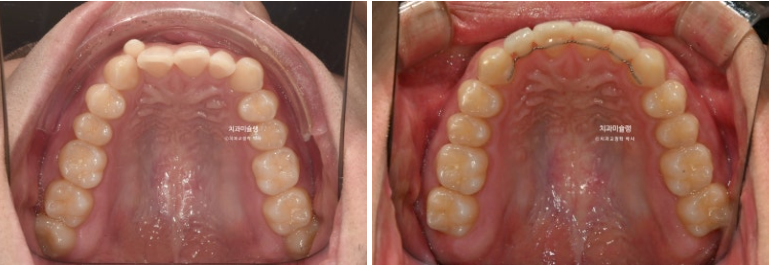

24.03~25.11